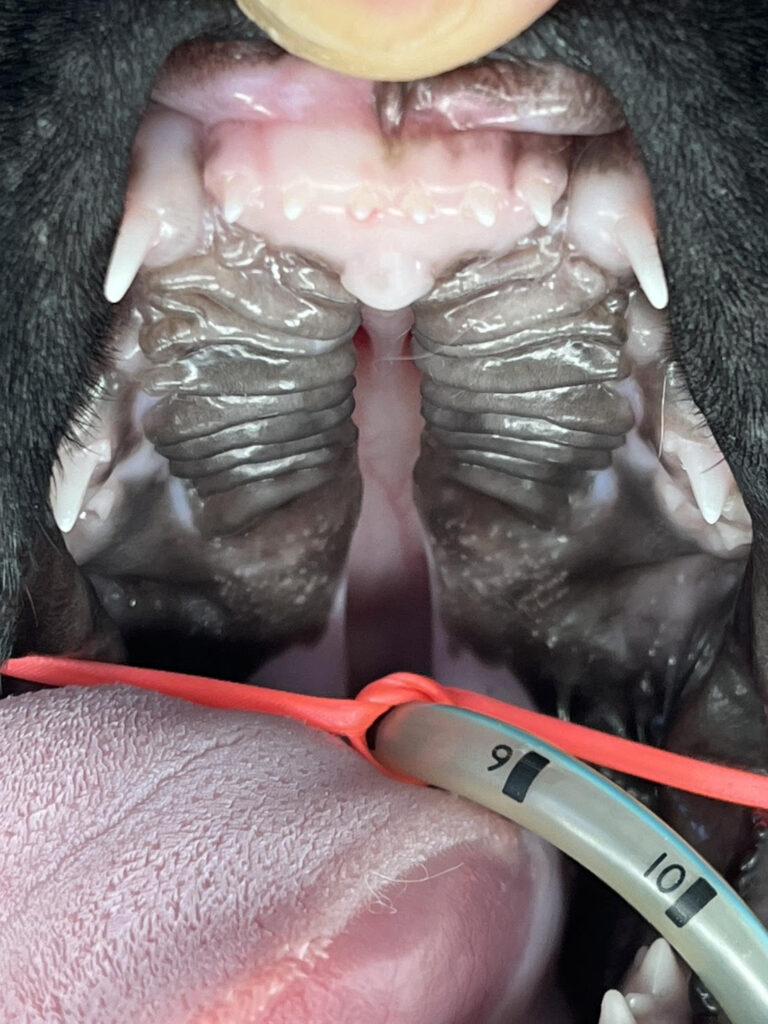

口蓋裂の治療について

口蓋裂の手術は「すぐに」というわけにはいきません。

教科書的には生後2〜3ヶ月まで成長を待ってから手術のタイミングを検討します。

それまでの間はカテーテルによる給餌や、 特別な哺乳方法で栄養をしっかり摂らせて元気に成長してもらいま す。

手術は技術的に難しく、再手術が必要な場合もありますが、適切なタイミングで行えば多くの子が普通の生活を送れるようにな ります。